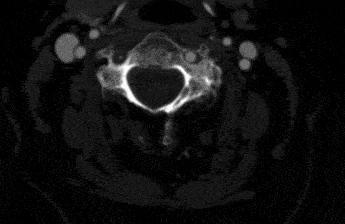

You cannot diagnose a clot in a neck artery without imaging. Imaging means taking pictures of the artery to see if there is a clot. The easiest test is an ultrasound. A carotid artery ultrasound will be able to show blockages in the neck arteries.

Sometimes ultrasound can even show a dissection, but it is not the best test for this purpose. If you need more accurate pictures, you will choose a CT scan or an MRI. In most places it is easier to get a high quality CT scan. A CT scan of the neck arteries will show blockages and any other problems that might exist there. It is very accurate.